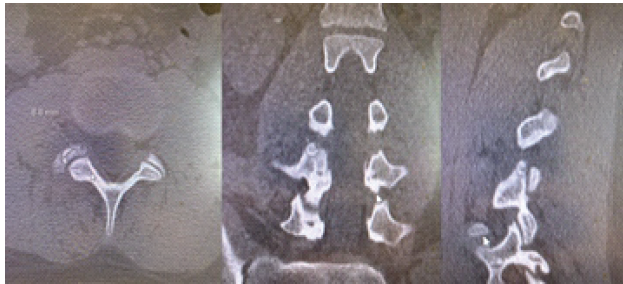

Given the non-specific MRI findings, a computed tomography (CT) scan was obtained. CT revealed a rounded lesion in the right superior articular process of L4, measuring 9 × 9 mm, with surrounding sclerosis and a central lucent nidus. The lesion was located at the level of the facet joint, consistent with OO (Fig. 1).

Figure 1: Computerized tomography scan of the L4 superior articular process osteoid osteoma.